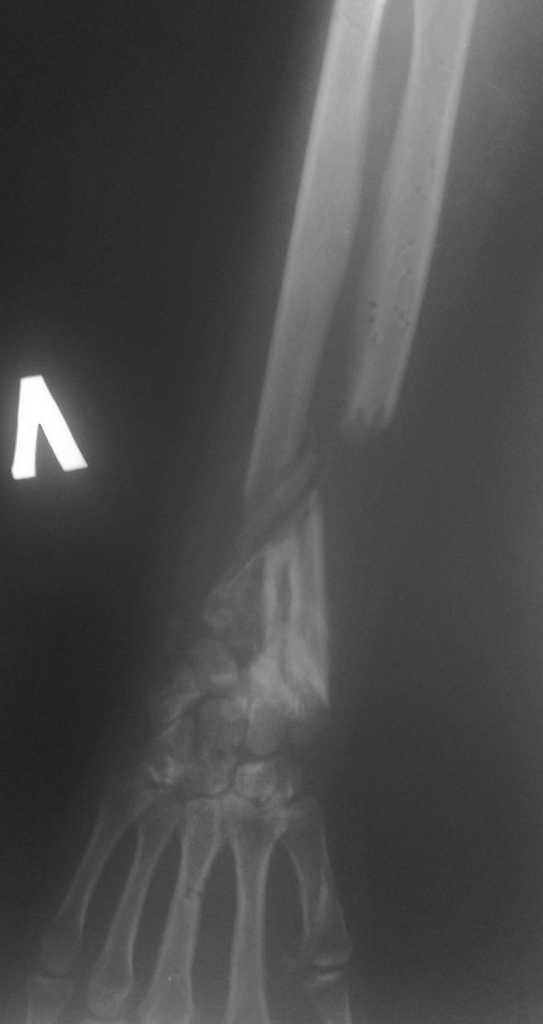

Имеется постттравматический дефект дистальных отделов костей левого предплечья.

Больная Д. 30 лет плучила травму 12.07.09г, пассажир скутера - тяжелая сочетанная травма брюшной полости и конечностей, гемоперитониум, закрытый перелом н\3 ЛЕВОГО БЕДРА, открытый перелом н/3 левого предплечья с дефектом обеих костей, рана голени. С момента травмы перелом предплечья был фиксирован анкерно-спицевым апаратом, проводилось лечение других сегментов. В настоящий момент АВФ демонтирован, имеется следующая рентгенологическая картина (см. приложение), имеется дефект обеих костей и суставных поверхностей. Коллеги подскажите варианты лечения в данном случае ?!